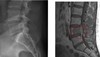

Vad ser du på denna skelettröntgen till vänster?

- Sänkt ledspalt vänster (jämför med höger) och osteofyt vänster

Vad ser du på denna skelettröntgen till höger?

- Ingen ledspalt kvar

- Deformation av talus (bild omformat)

- Liksom Benatrition

- Osteofyter inringat

- Subkondral skleros (vitare intill del)

- Subkondrala cystor (inringad uppklarning intill led) – benigna